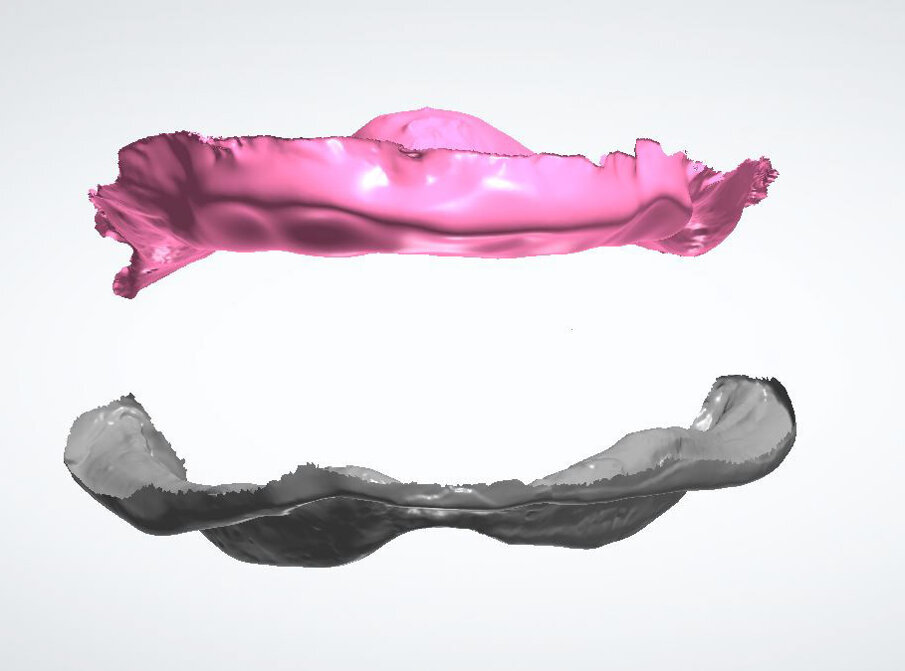

Fig. 4_Scansione intraorale superiore e inferiore.

Fig. 6_La protesi superiore e inferiore disegnate con le librerie Ivoclar Ivotion.